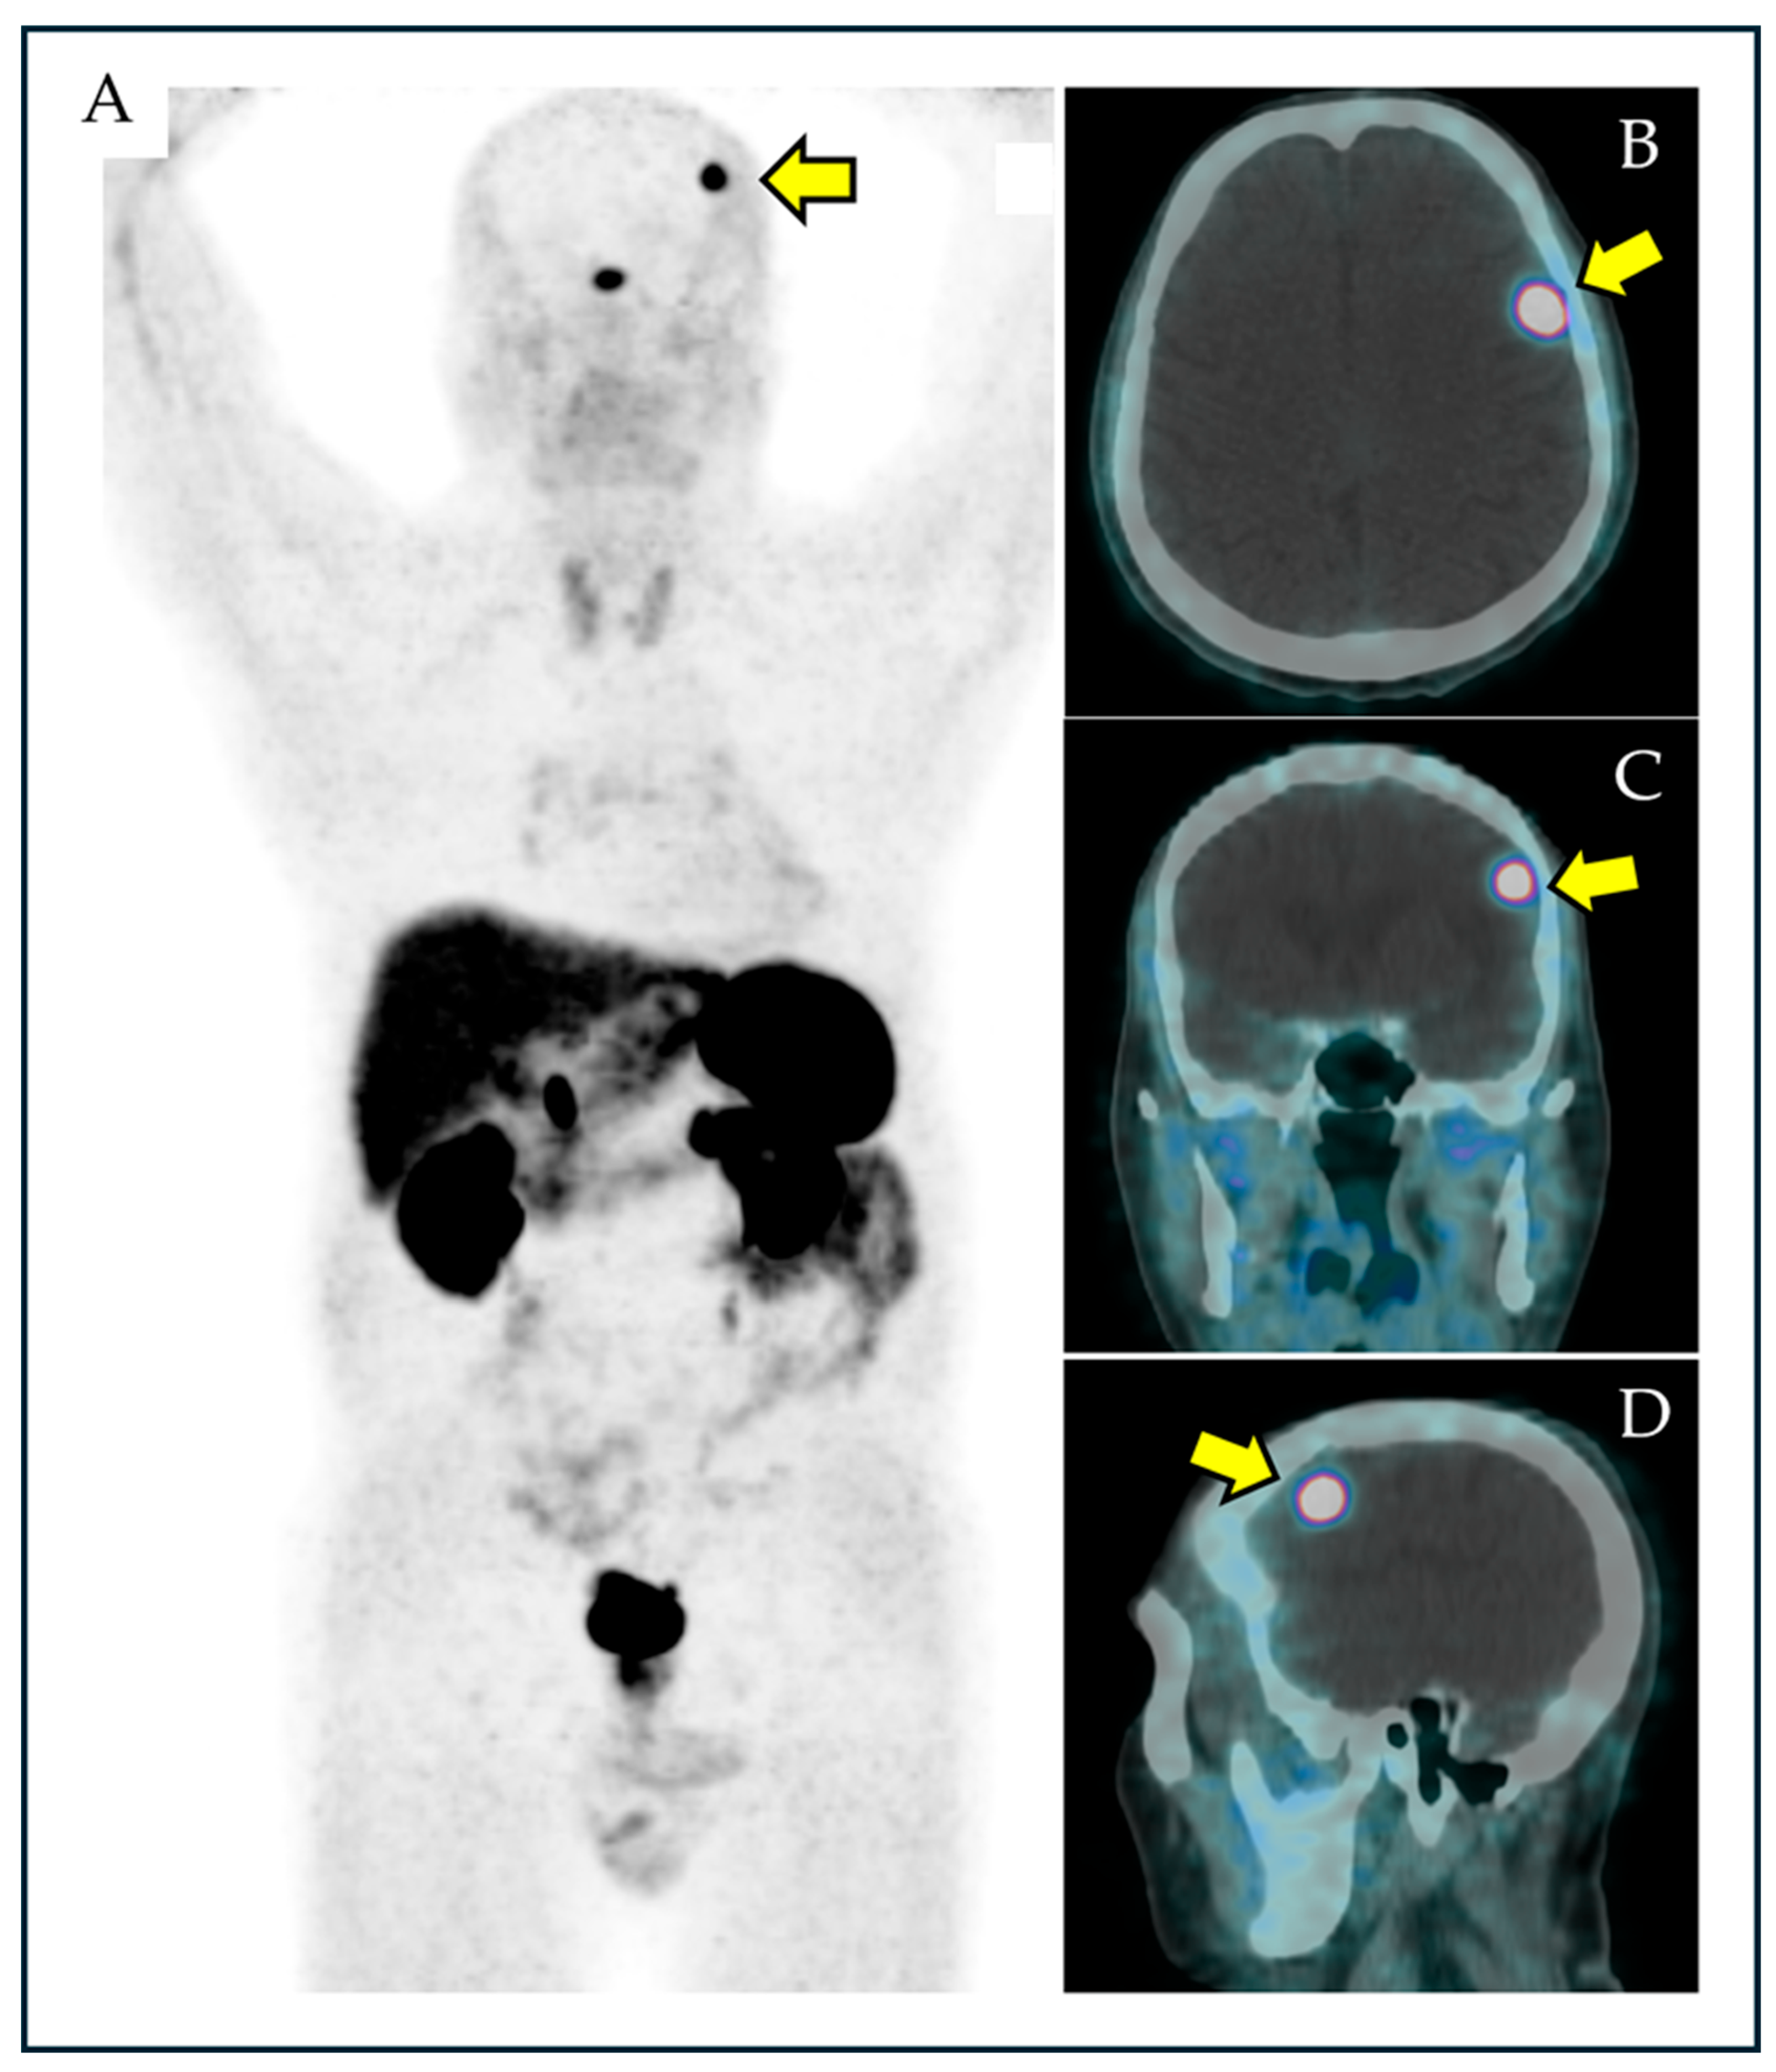

- Umana, G.E.; Ferini, G.; Harikar, M.M.; Venkataram, T.; Costanzo, R.; Scalia, G.; Palmisciano, P.; Brunasso, L.; Paolini, F.; Sciortino, A.; et al. Detection of “Incidentalomas” on Brain and Body 68Ga-DOTATOC-PET Scans: A Retrospective Study and Case Illustration. Anticancer Res. 2022, 42, 5867–5873. [Google Scholar] [CrossRef]

- Albano, D.; Treglia, G.; Dondi, F.; Bertagna, F. Prevalence of Brain Incidental Lesions Detected by 68Ga-DOTA Peptides PET/CT. Medicina 2022, 58, 916. [Google Scholar] [CrossRef]